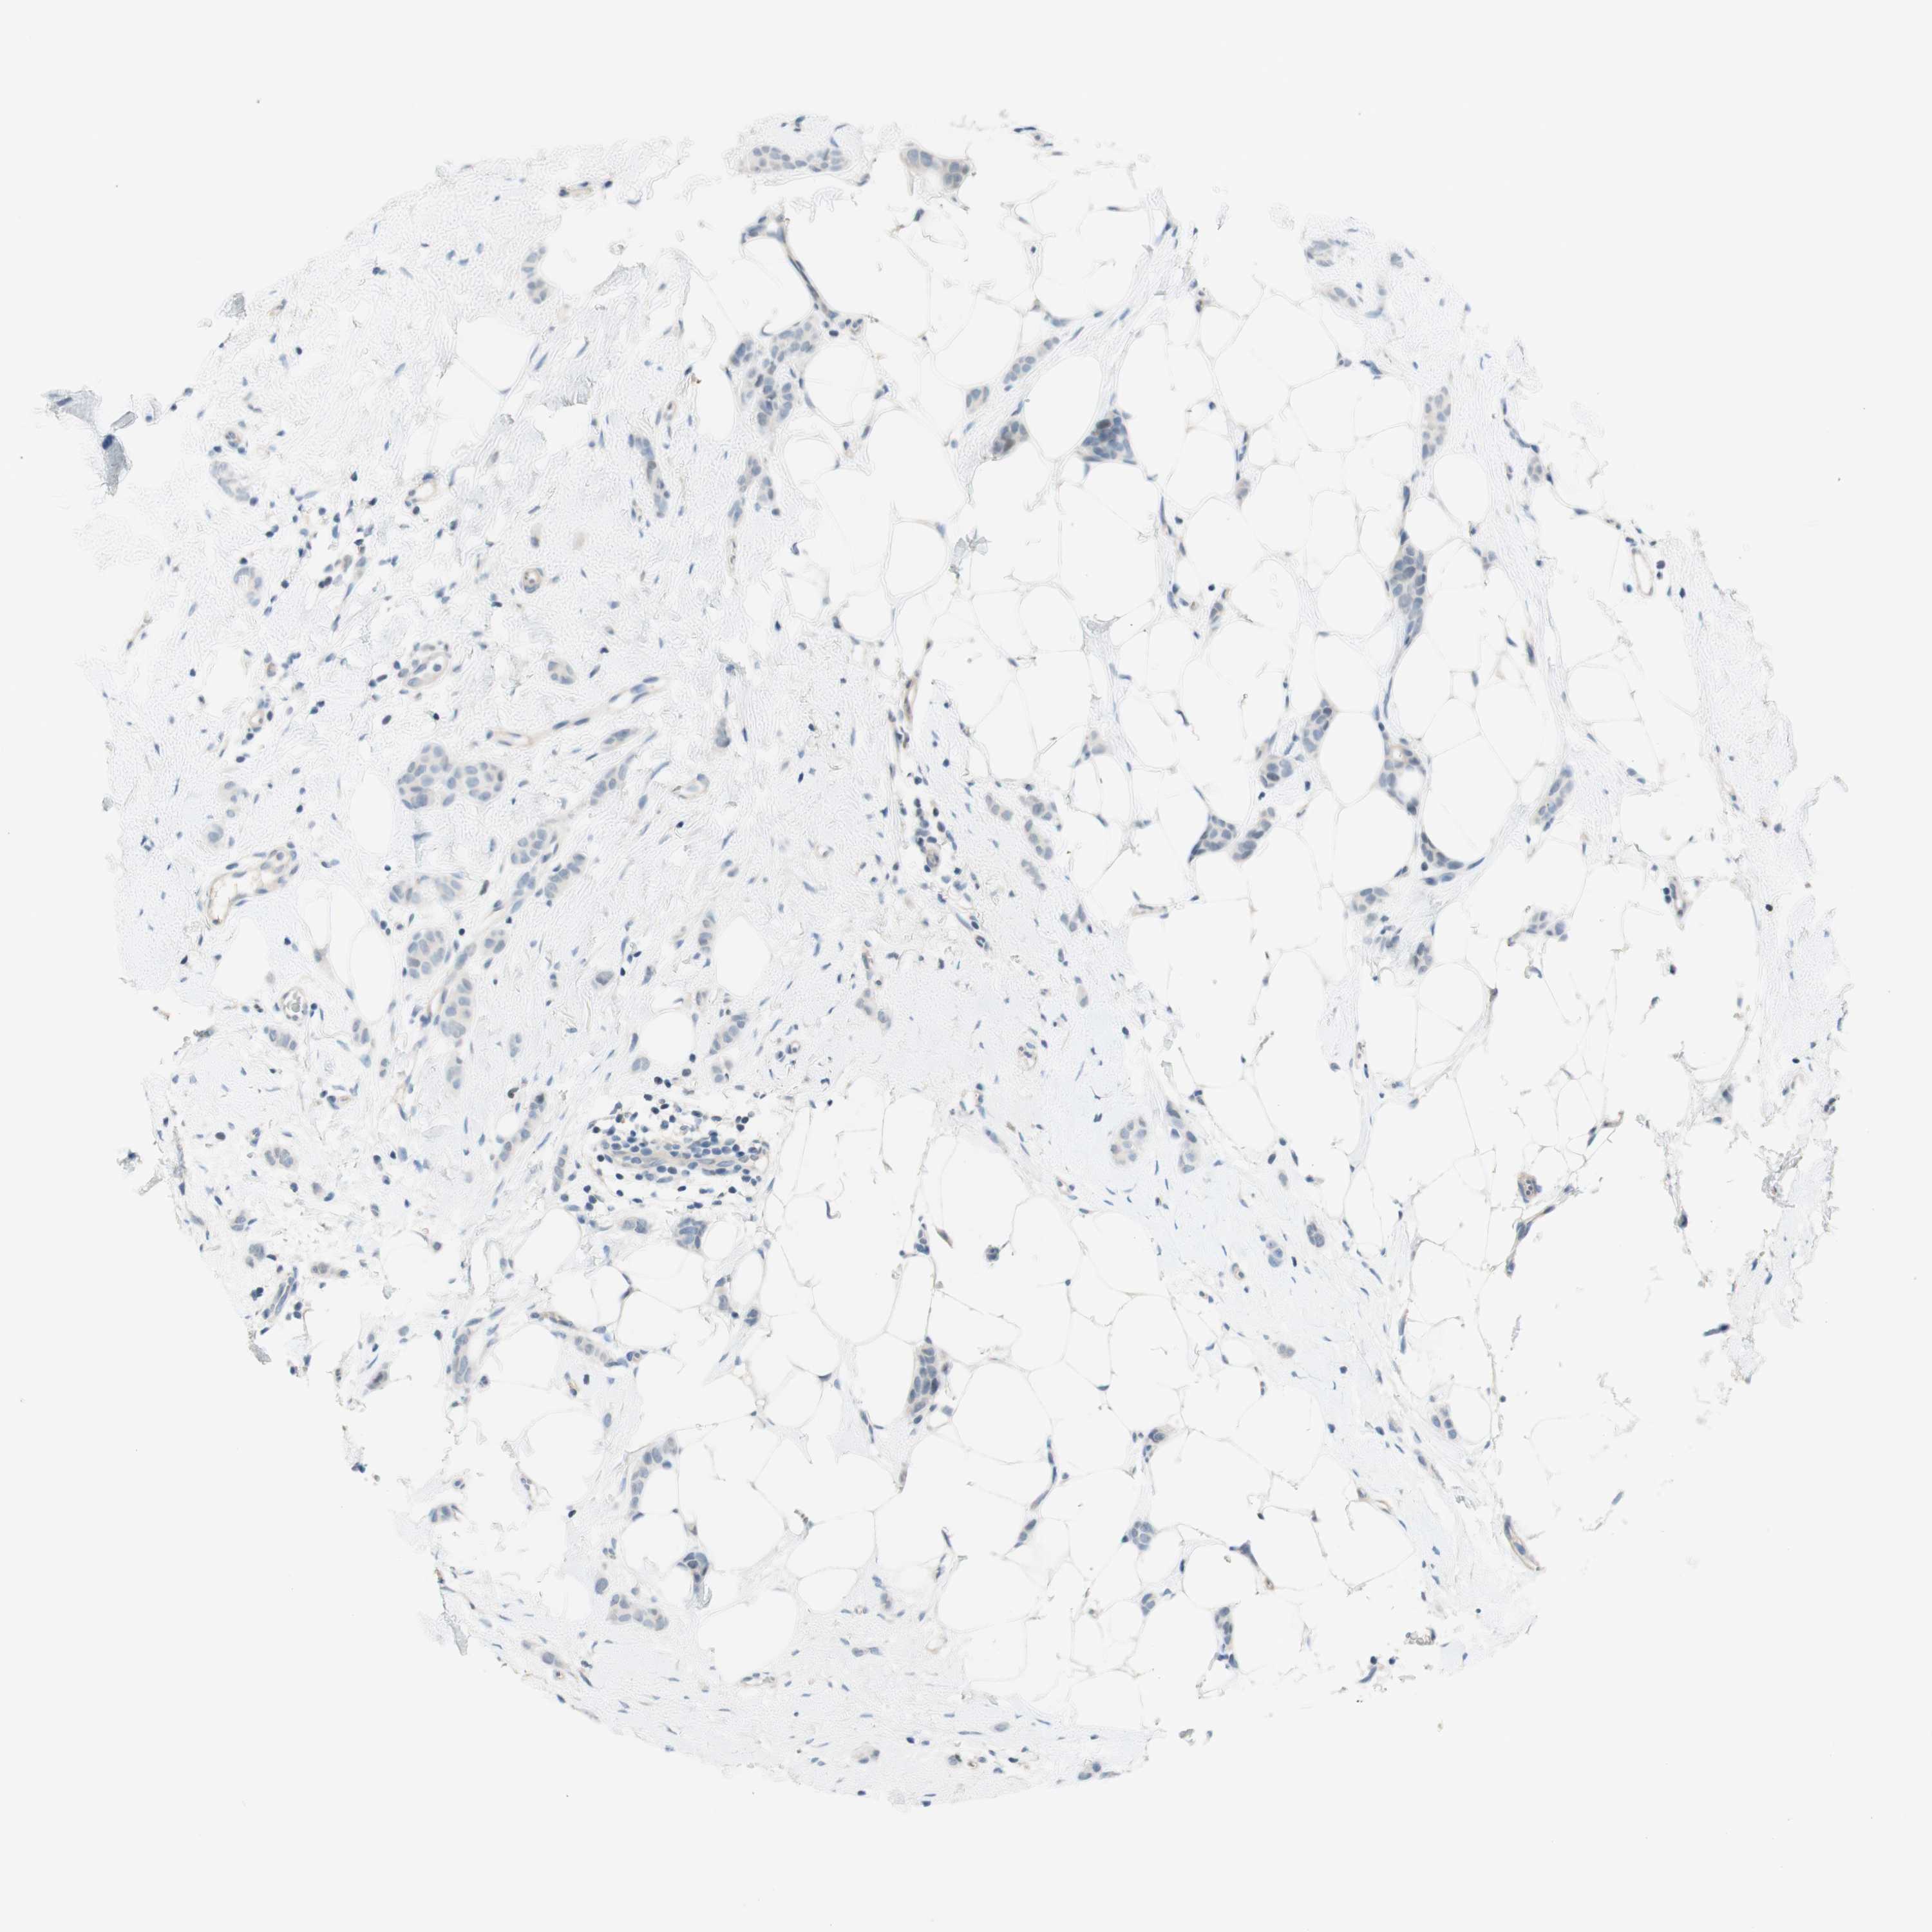

CANCER BREAST CANCER Show tissue menu

BRCA TCGA BRCA VALIDATION PROTEIN EXPRESSION

ANTIBODIES